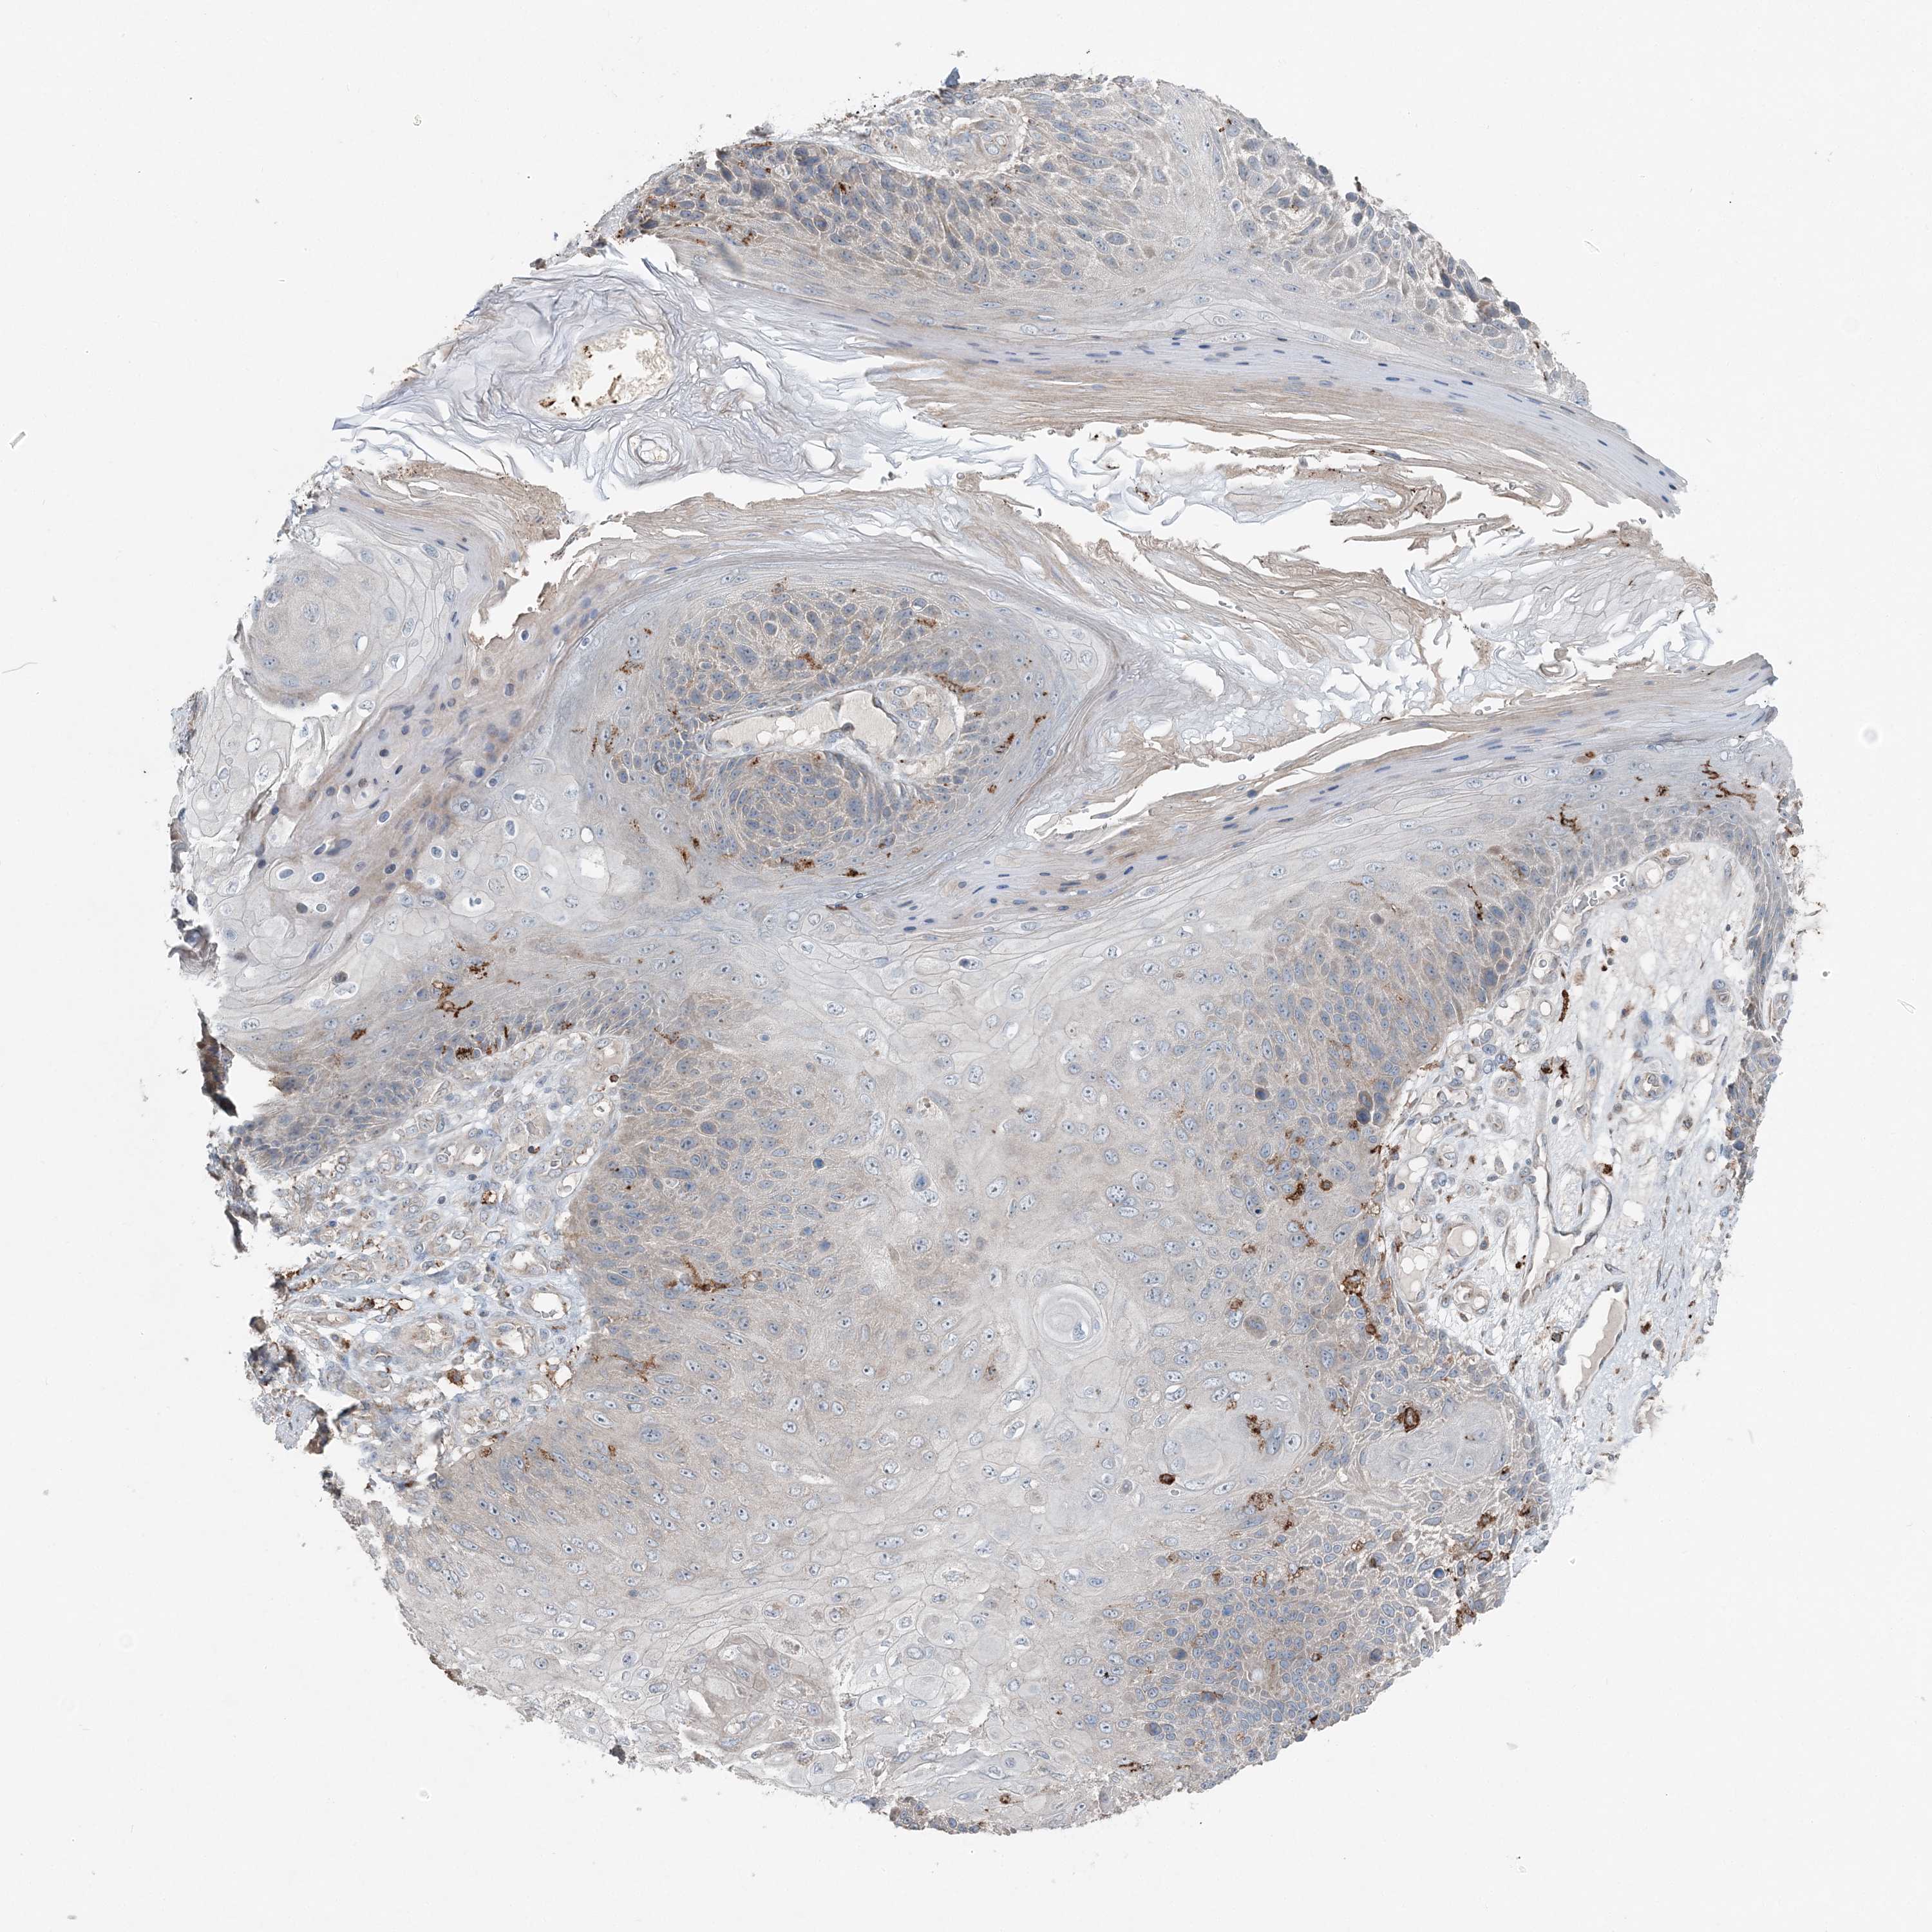

SKIN CANCER - Protein expressioni

A mouse-over function shows sample information and annotation data. Click on an image to view it in a full screen mode. Samples can be filtered based on level of antibody staining by selecting one or several of the following categories: high, medium, low and not detected. The assay and annotation is described here.

Antibody stainingi

Antibody staining in the annotated cell types in the current human tissue is reported as not detected, low, medium, or high, based on conventional immunohistochemistry profiling in selected tissues. This score is based on the combination of the staining intensity and fraction of stained cells.

Each image is clickable and will lead to virtual microscopy that enables deeper exploration of all samples and also displays staining intensity scores, fraction scores and subcellular localization as well as patient and tissue information for each sample.

Antibody HPA036492

Basal cell carcinoma